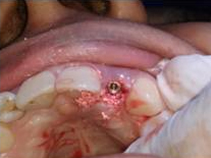

Implant with bone Graft

Placement of Bone Grafting